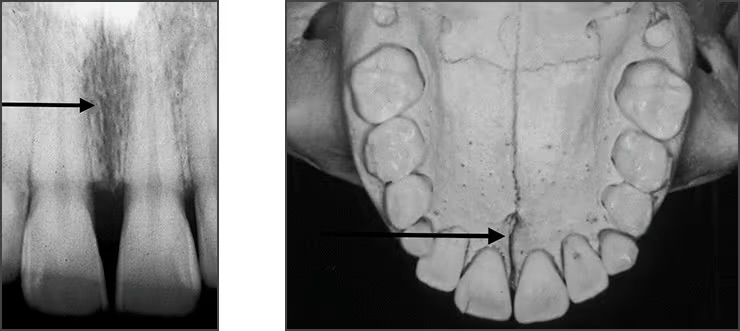

Incisive foramen / nasopalatine foramen

Appears between the roots of the central incisor & looks like a round oval less than 1 cm in diameter

Seen on maxillary central incisor PA’s

Median palatine suture

Appears as a thin vertical line in the midline on max central incisor PA’s

Is where the two halves of the maxillary come together